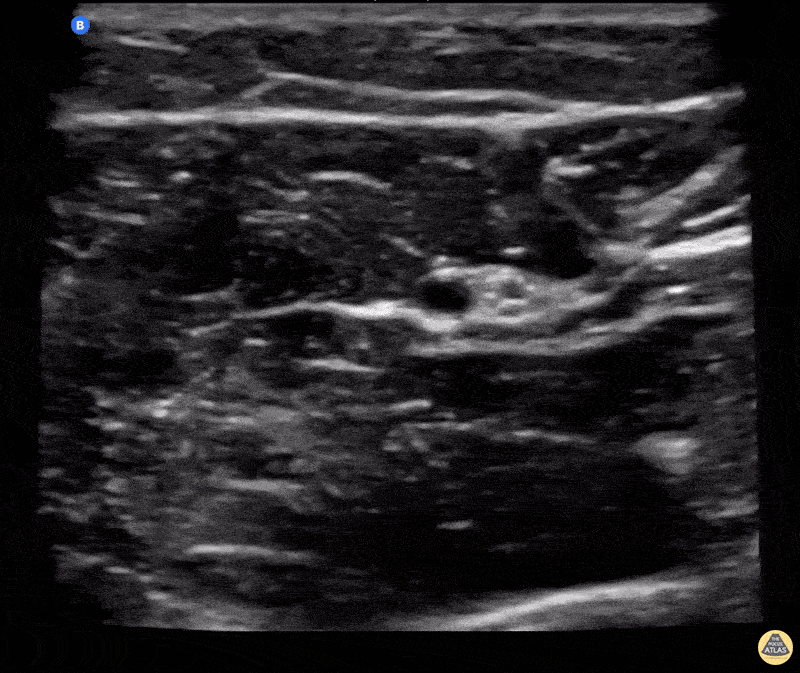

37 yo female presented with hand pain and deformity after punching a wall. XR and clinical exam showed displaced and rotated 5th MC fracture which required reduction prior to splinting. Ulnar nerve block was performed with needle in plane under US guidance. Nerve is located ulnar to the ulnar artery in the mid forearm and needle path is from lateral to medial. Following the block, reduction performed without any pain and patient was discharged with hand surgery follow up on outpatient basis with near anatomic positioning following reduction and splinting. Miguel F. Agrait MD CAQ-SM, Tatiana Vargas PGY-3 Centro Médico Episcopal San Lucas, Ponce PR